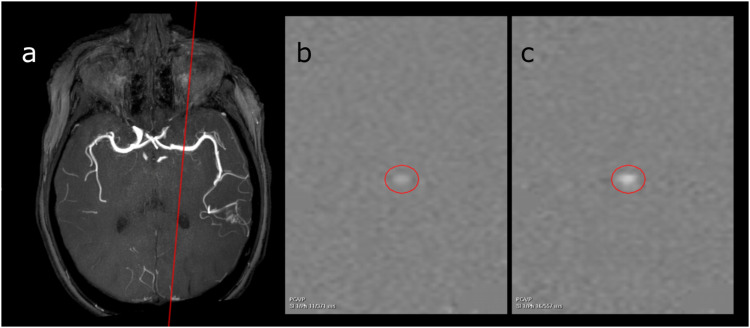

Materials and methods: Highest flow (HF), lowest flow (LF), mean flow (MF), peak systolic velocity (PSV), end-diastolic velocity (EDV), and mean velocity (MV) were measured in feeding arteries in patients with intracranial AVMs using 2D PC-MRI at 3 T. Measurements were compared to previously reported values in healthy individuals. Values in patients above the 95th percentile in the healthy cohort were categorized as pathological. Nidus volume was measured using 3D time-of-flight MR angiography.

Abstract Image